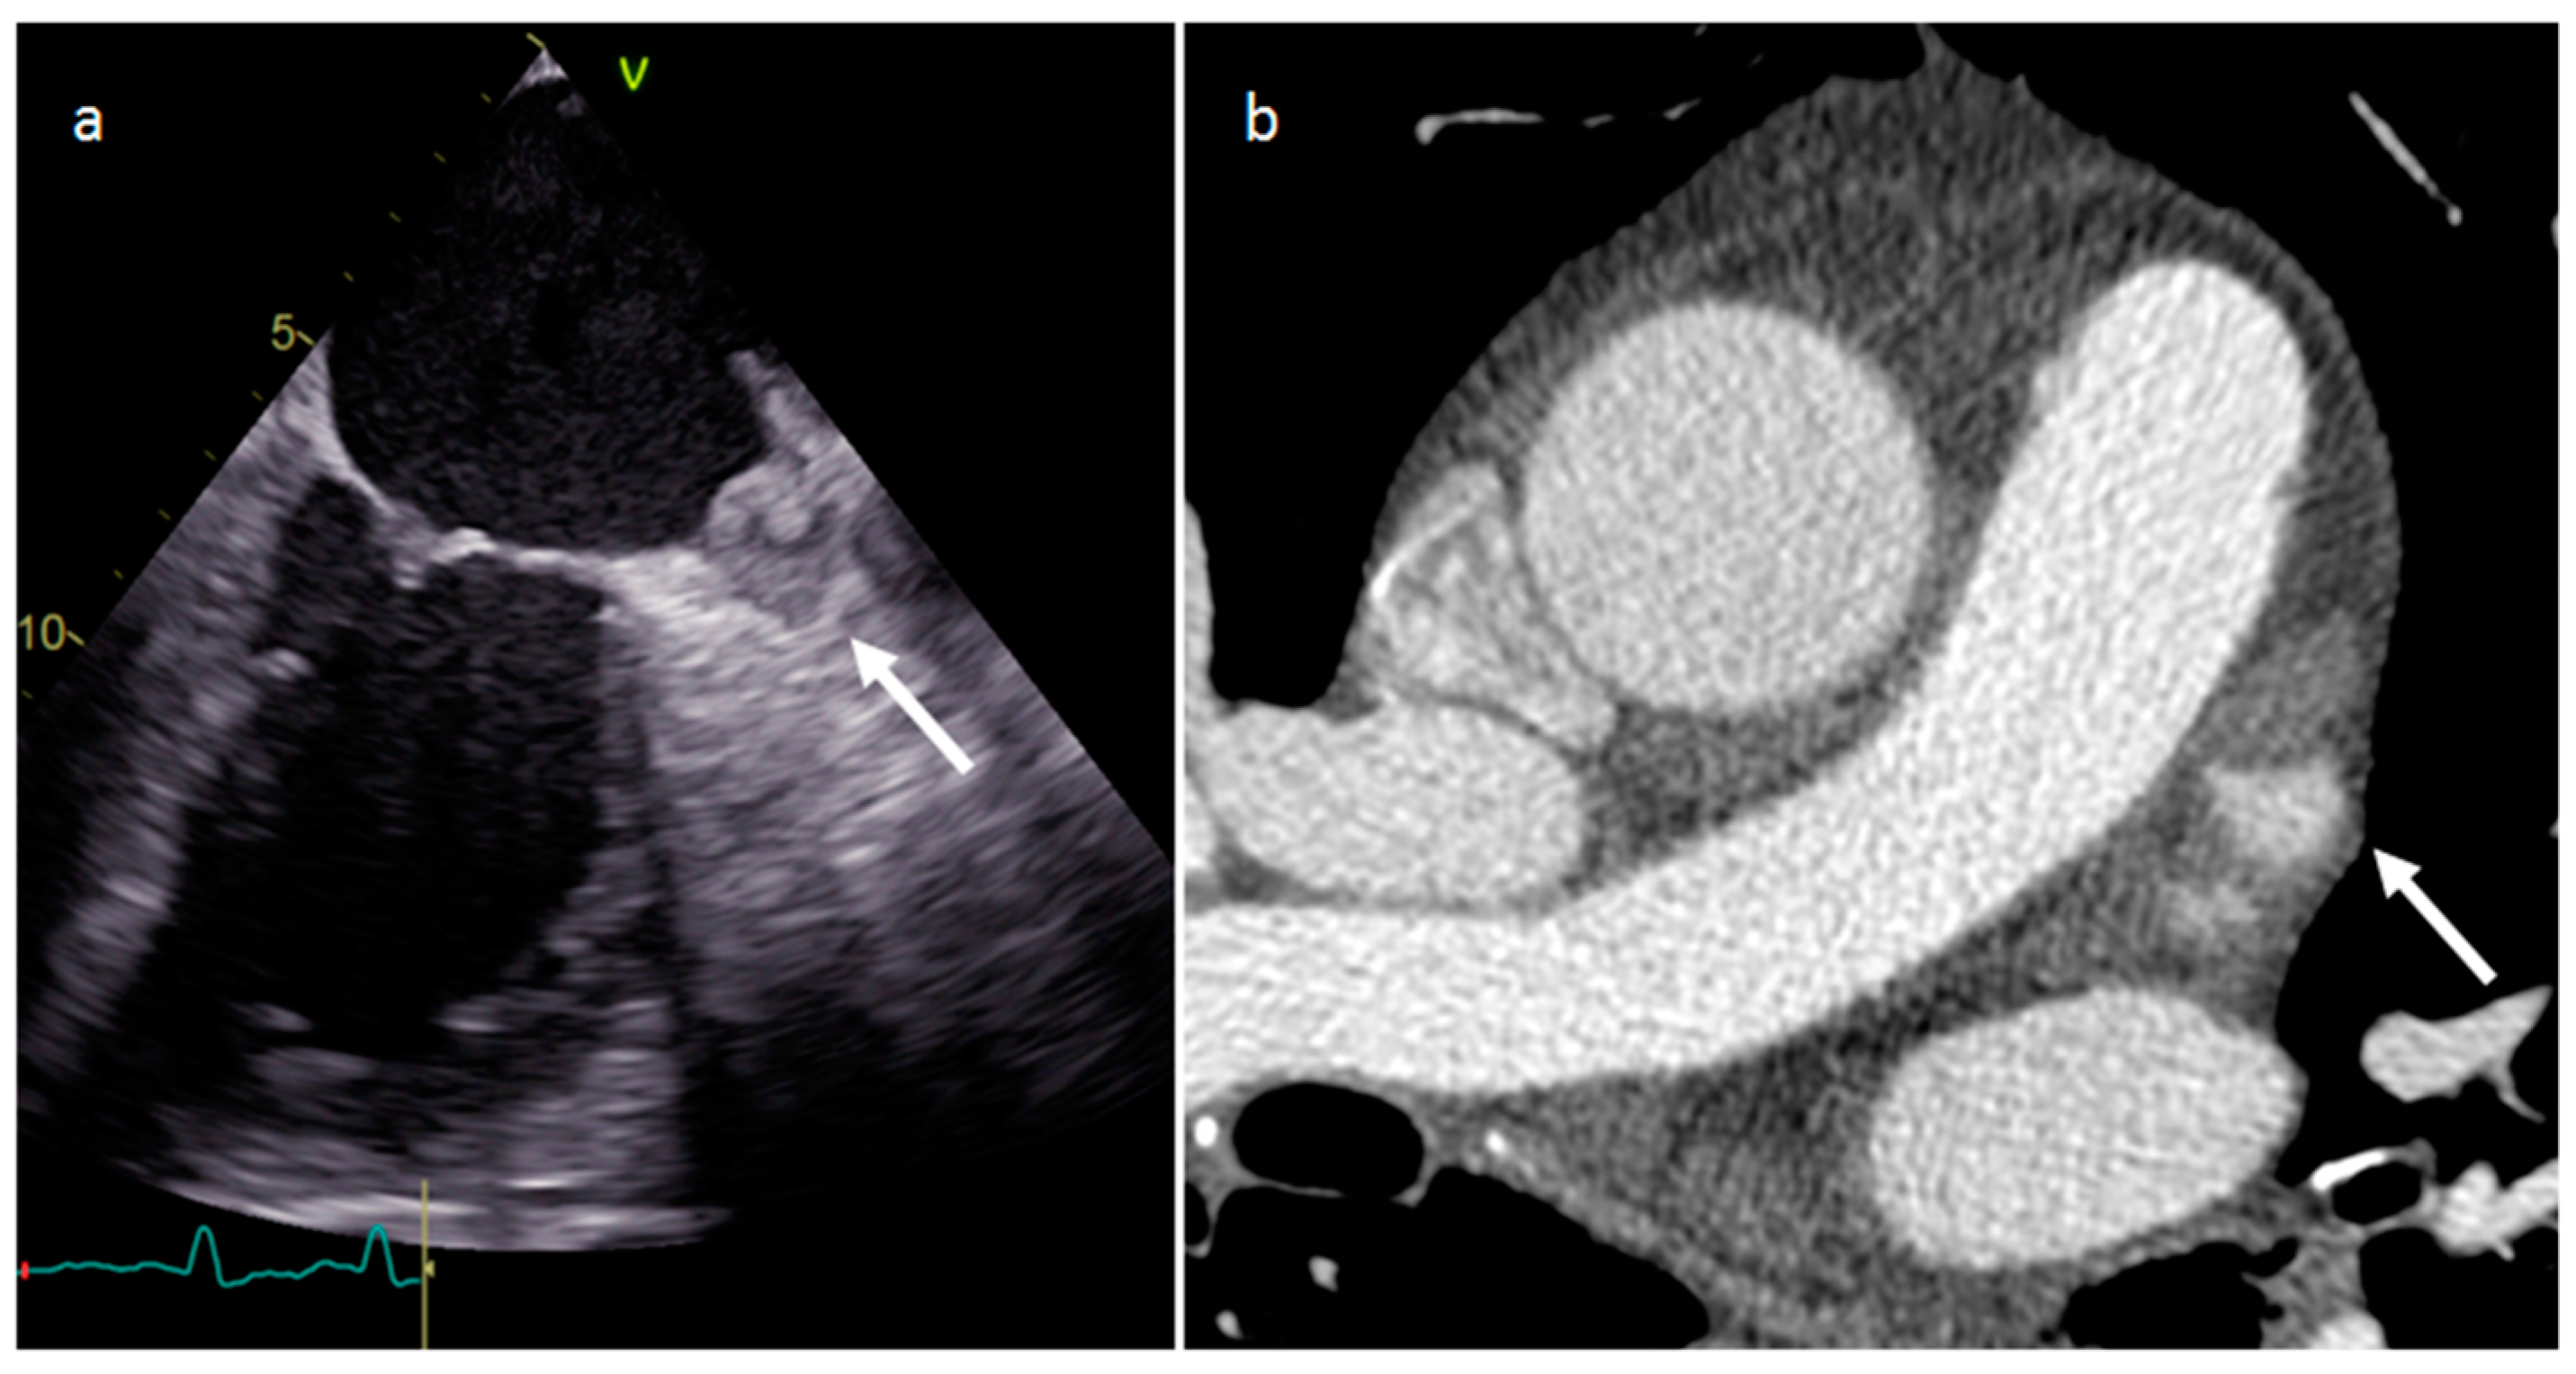

3.1. Thrombus

| Thrombus | Adulthood | LA, LAA (AF) LV (MI) | Asymptomatic, embolic events | Non-enhancing Intracardiac lesion | Acute: Low echodensity, rounded with smooth contours Chronic: High echodensity, linear or crescentic lesions along the endocardial surface | Low attenuation, no contrast enhancement, chronic thrombus may be calcified Usefulness of delayed CT imaging, as in the LAA stasis of blood can simulate a thrombus on early arterial images | Acute: hyper T1w and T2w Subacute: hyper T1w and hypo T2w Chronic: low T1w and T2w No enhancement. |